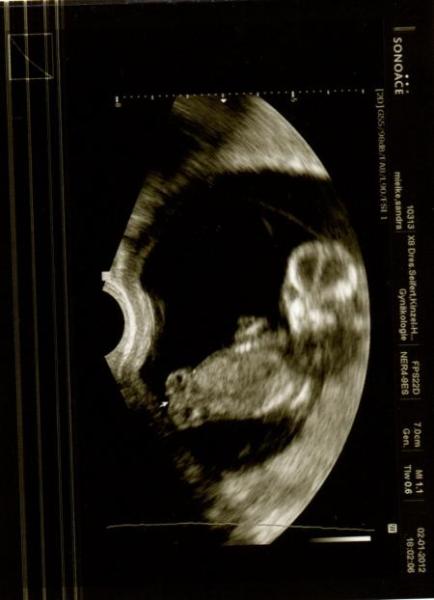

noch mal ein 2tes Bild :o)

Bild zu

Hi Steffie, da drücke ich dir ganz doll die Daumen. Wir haben sogar 4 Bilder bekommen- aber die beiden finde ich am besten ;o) hast recht- hat auch immer die Beine weggedreht- so unterm Motto "lasst mich bloß in Ruhe" *GRINS* Es ist echt wahnsinn wie schnell die sich entwickeln-ein richtiges Wunder :o) Genieß das Babyfernsehn morgen :o)